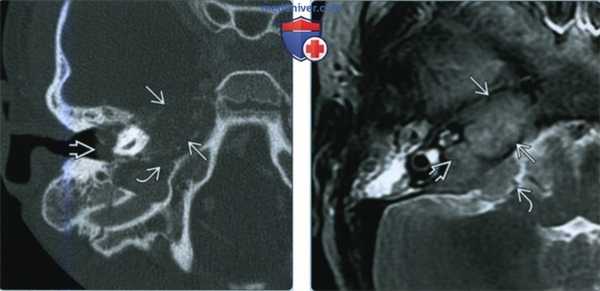

(Слева) При КТ височной кости у младенца с правосторонним параличом ЧН VII определяется литическая, пермеативная деструкция вершины пирамиды; плотная костная слуховая капсула интактна. Опухоль распространяется в полость среднего уха и обусловливает эрозию передней стенки яремного отверстия.

(Справа) При аксиальной MPT Т2 ВИ FS у этого же пациента определяется гипоинтенсивное образование вершины пирамиды, сопоставимое с целлюлярной опухолью, распространяющейся в правый ВСК и мосто-мозжечковый угол. При биопсии подтвердилась нейробластома. При последующих исследованиях обнаружилась первичная опухоль надпочечника.